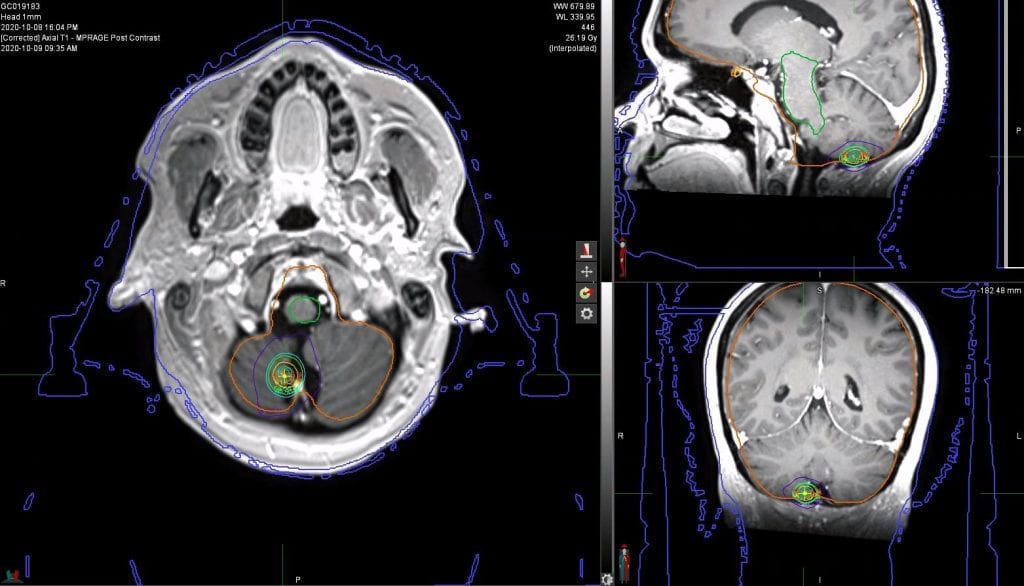

A 37-year-old lady with a diagnosis of metastatic adenocarcinoma of the lung (EGFR mutation positive (Exon 19 deletion)) with brain, node and ovarian metastases since 2018 had previously been treated with WBRT in 2019 followed by Carboplatin/Paclitaxel, which was stopped due to toxicity. She was switched to Osimertinib in February 2019. MRI head in September 2020 showed a new solitary brain metastasis in the right cerebellum with a PET scan showing stable extra-cranial disease. The patient was treated at GenesisCare in Oxford with SRS and, currently remains well and symptom-free. Follow up imaging showed a very good radiological response at six months.

Figure 1. Isodose coverage of right cerebellar metastases (axial, sagittal and coronal views).